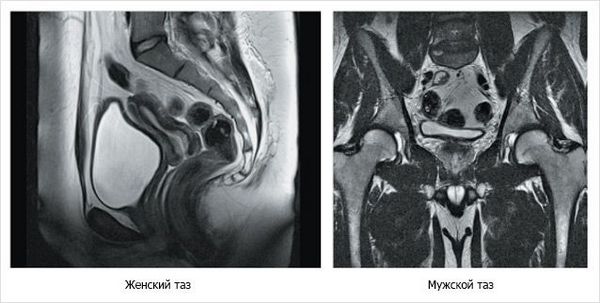

Томография органов малого таза - это один из новейших методов исследований на рынке диагностических услуг. Томографическое исследование позволяет проводить диагностику заболеваний методом послойного изображения внутренних органов, за счет чего доктору удается получить наиболее достоверную информацию о наличии различного патологического процесса в органах, системах. Томограмма делится на два принципиально отличающихся между собой метода исследования - это компьютерная томография, базирующаяся на рентгенологическом излучении и магнитно-резонансная томография, основанная на методе магнитного резонанса с взаимодействием атомов водорода в человеческом организме. Тот и другой способ исследования являются неинвазивными принципами диагносцирования, какой вид томографического исследования назначить пациенту для данной системы, определяет врач, опираясь на клиническую картину, а также индивидуальные особенности самого больного.

- Результаты. Что же касается оценочной характеристики результатов, то компьютерная томограмма системы внутренних органов как у мужчин, так и у женщин, проводится чаще для получения хорошей визуализации сосудистых структур. Магнитно - резонансный метод позволяет выявить самые трудноуловимые различия мягких тканей, опухоли, кисты, например, матка и яичники или предстательная железа.